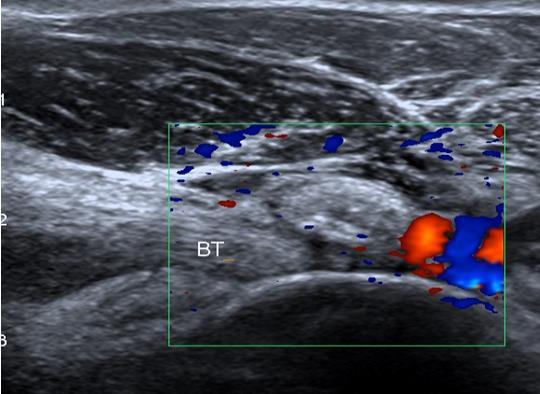

BICIPITORADIAL BURSITIS:

the normal bursa surrounds the tendon in supination, and passes between the tendon and radial tuberosity in pronation, allowing tendon glide

bursitis can accompany biceps tendinosis and tears or be a stand-alone diagnosis. It typically causes swelling and anterior elbow pain

Fig. 8 Long section ultrasound image showing distal biceps tendinosis and bicipitoradial bursitis. The tendon is abnormally thickened and hypoechoic (red arrows) and there is fluid around the insertion in the bicipitoradial bursa (green arrow).

Fig. 9 Axial MRI showing thickened biceps tendon with fluid in the surrounding bicipitoradial bursa (red arrow).